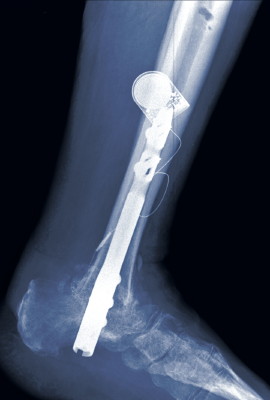

The first case involved a 63-year-old female who had a tibial-talar nonunion despite two previous attempts at treatment by another clinic. The patient subsequently developed a severe malposition secondary to progressive posterior tibial tendon dysfunction (PTTD). The correction entailed a tibial-calcaneal arthrodesis with intermetatarsal nail, external fixation and implantable direct current bone stimulation. She achieved good consolidation at just eight weeks postoperatively.

The second case involved a 49-year-old female with severe longstanding post-traumatic multilevel deformity. This patient had undergone 21 previous surgeries on her leg/foot for limb salvage over a 15-year period. In regard to her final reconstruction procedure, surgeons corrected the ankle deformity first and subsequently performed an open ankle arthrodesis. At 10 weeks after the attempted arthrodesis, she had obvious delayed union. The final radiograph shows good union at eight weeks after we applied a PEMF device.